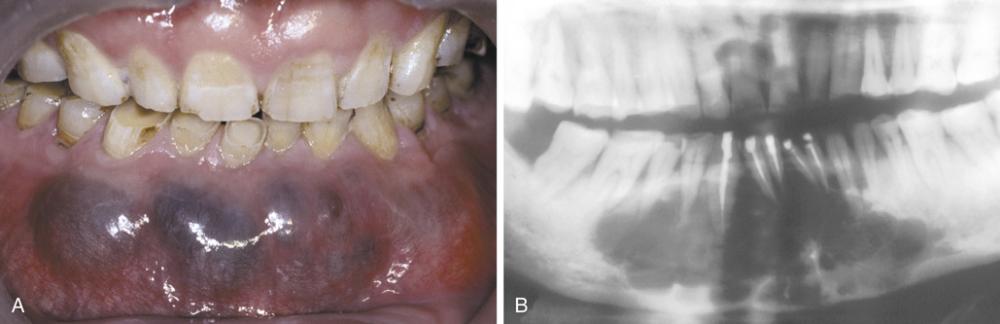

- Expansion of the posterior maxillary alveolus caused by a large pink lesion.

- Panoramic radiograph showing a large radiolucency with a small calcified structure is seen in the lower portion.

calcifying odontogenic cyst